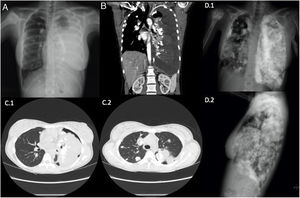

Radiografía simple de tórax PA A) y tomografía computarizada toraco-abdominal corte coronal B) al diagnóstico, donde se objetiva derrame pleural izquierdo masivo, lesión blástica en cabeza humeral derecha, múltiples imágenes de densidad calcio en parénquima pulmonar bilateral y pleura. TC de tórax corte axial C1 y C2) tras drenaje de derrame pleural, donde destacan múltiples metástasis bilaterales en parénquima pulmonar y en pleura, así como neumotórax izquierdo. Radiografía simple de tórax PA y lateral D.1 y D.2) a los 10 meses desde el diagnóstico, donde se demuestra un aumento en número y tamaño de los nódulos y masas pulmonares y pleurales bilaterales, derrame pleural izquierdo y aumento de la lesión primaria en cabeza humeral derecho.

Los tumores óseos primarios representan menos del 0,2% de las neoplasias malignas, siendo el osteosarcoma el más frecuente1. Las metástasis pulmonares son las más habituales y, junto con elevación de la LDH y la FA, son factores de mal pronóstico. La agresividad de la afectación pulmonar de este tumor queda ilustrada en esta imagen clínica2.